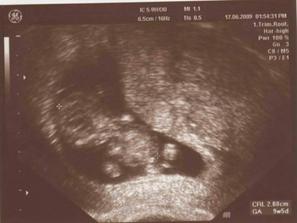

17.6.09: jsme 9tt+5, prcek je velký 2,88 cm a už mám komplet tělíčko i s prstíky viz obrázek z UTZ